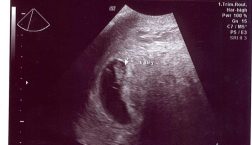

Hey everyone, Happy fall!! I am tremendously happy that it’s finally time for hoodies, smore’s, bonfires, hay rides, etc. I love to see the leaves changing colors and falling! It is by far my favorite season. I’m sorry that I have been on a blogging hiatus, but there is a good reason. I have just […]